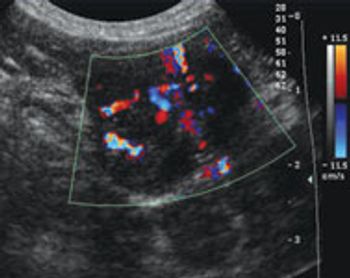

Thrombosis is a complication of many diseases in veterinary medicine.